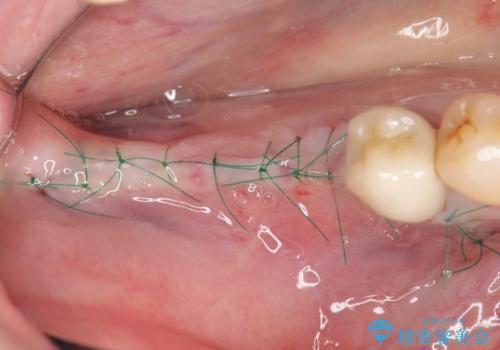

骨の造成を同時に行うインプラント治療

骨は薄くなってしまい、インプラントの長期的な安定を見込むには不十分でしたのでインプラントの埋入と同時に周囲にコツの造成を行う治療計画を立てます。

入れ歯に替わりインプラント治療を行ったことでしっかりと物が噛め、食事ができるようになり大変喜んでいただくことができました。